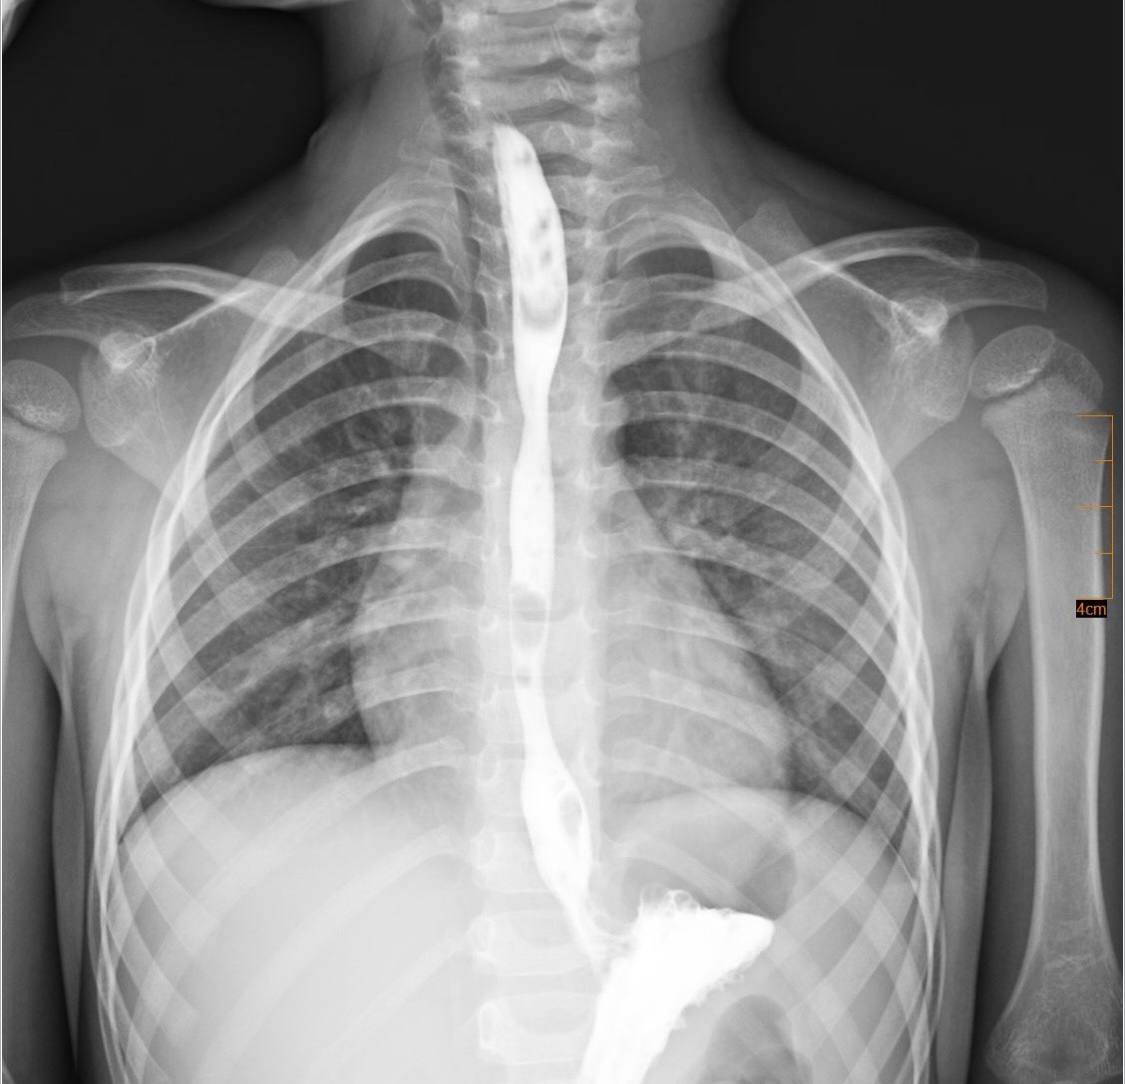

Дитина випадково проковтнула хімічну речовину з категорії побутової хімії, що призвело до тяжкого хімічного опіку стравоходу. На момент госпіталізації стан дитини був вкрай важким: вона не могла самостійно приймати їжу, страждала від вираженого болю, слинотечі та блювання. Малечу негайно госпіталізували до відділення інтенсивної терапії.

Згодом у дитини сформувався критичний стеноз стравоходу – значне звуження його просвіту, що повністю унеможливлювало прийом їжі через рот.

Після ретельного обговорення мультидисциплінарною командою було ухвалено рішення про проведення серії балонних дилатацій стравоходу – малоінвазивних ендоскопічних втручань, під час яких звужену ділянку поступово розширюють спеціальним балоном без виконання розрізів.